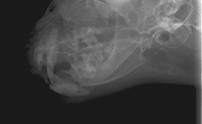

眼球摘出、眼瞼腫瘤切除、チェリーアイ整復、眼瞼縫合、瞬膜フラップ、眼球突出整復、耳介切除、垂直耳道切除、総耳道切除、鼻鏡切除、口腔腫瘍切除(上顎骨切除、下顎骨切除を含む)、各種抜歯(猫の全臼歯抜歯含む)舌腫瘍切除、唾液腺嚢胞切除、皮膚腫瘤切除、断脚(前肢、後肢、片側骨盤切除)、断尾、肺葉切除、胸腺腫切除、心膜切除、横隔膜ヘルニア整復、肝臓腫瘍切除、胆嚢摘出、胃切開、胃拡張胃捻転症候群整復、胃腫瘍切除、腸管切開、腸管腫瘍切除、直腸腫瘍切除(粘膜、全層プルスルーなど)、腎臓摘出、SUB設置手術、脾臓摘出、副腎摘出、膀胱切開、膀胱腫瘍切除(部分切除、全摘出、膀胱尿道一括切除など)、卵巣腫瘍切除、精巣腫瘍切除、卵巣子宮全摘出、肛門嚢切除、各種骨折、膝蓋骨脱臼整復、股関節脱臼整復、大腿骨頭切除、椎間板ヘルニア(各種椎弓切除術)、各種リンパ節切除 など